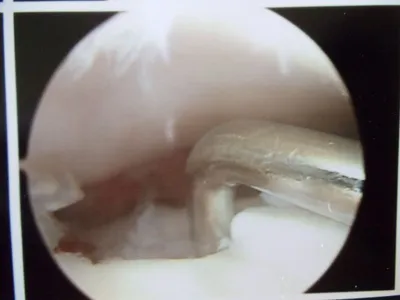

Pic of an OCD in the talar dome due to pressure from the nodule.

Pic after microfracture and debridement of above OCD.